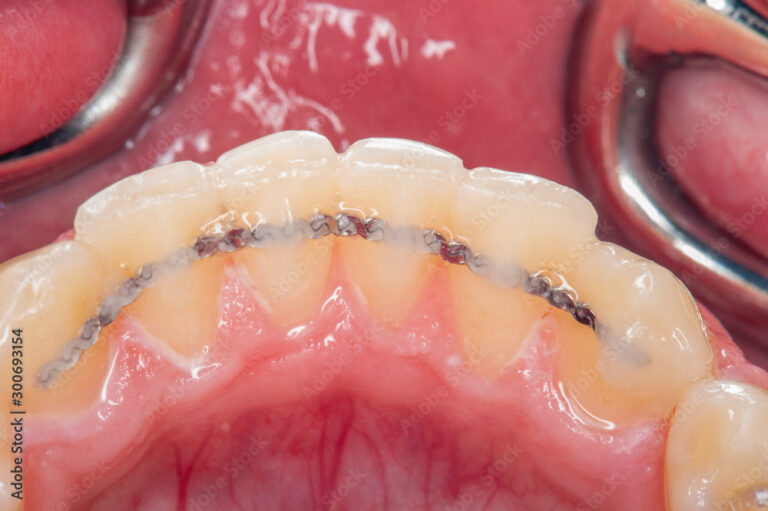

Der geklebte Retainer

Es handelt sich um einen dünnen Draht, der zur zusätzlichen Retention auf die Innenseite der Ober- bzw. Unterkieferfrontzähne geklebt wird. Er ist somit praktisch unsichtbar und kann einige Jahre im Mund belassen werden. Wenn sich eine Klebstelle lösen sollte, werden die Patient:innen angewiesen, sofort für eine Reparatur in die Ordination zu kommen.